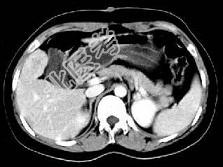

- 单项选择题根据所提供的图像,最可能的诊断为 ( )

A、肝平滑肌瘤

B、肝癌

C、肝血管瘤

D、局灶性结节增生

E、肝囊肿